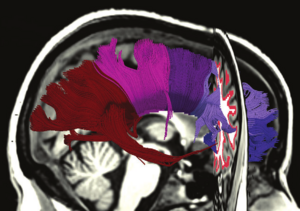

Seeing More by Showing Less: Orientation-Dependent Transparency Rendering for Fiber Tractography Visualization

Publication: PLoS One. 2015 Oct 7;10(10):e0139434. PMID: 26444010 | PDF Authors: Tax CM, Chamberland M, van Stralen M, Viergever MA, Whittingstall K, Fortin D, Descoteaux M, Leemans A. Institution: Image Sciences Institute, University Medical Center Utrecht, Utrecht, The Netherlands. Background/Purpose: Fiber tractography plays an important role in exploring the architectural organization of fiber trajectories, both in fundamental neuroscience and in clinical applications. With the advent of diffusion MRI (dMRI) approaches that can also model "crossing fibers", the complexity of the fiber network as reconstructed with tractography has increased tremendously. Many pathways interdigitate and overlap, which hampers an unequivocal 3D visualization of the network and impedes an efficient study of its organization. We propose a novel fiber tractography visualization approach that interactively and selectively adapts the transparency rendering of fiber trajectories as a function of their orientation to enhance the visibility of the spatial context. More specifically, pathways that are oriented (locally or globally) along a user-specified opacity axis can be made more transparent or opaque. This substantially improves the 3D visualization of the fiber network and the exploration of tissue configurations that would otherwise be largely covered by other pathways. We present examples of fiber bundle extraction and neurosurgical planning cases where the added benefit of our new visualization scheme is demonstrated over conventional fiber visualization approaches. Funding: